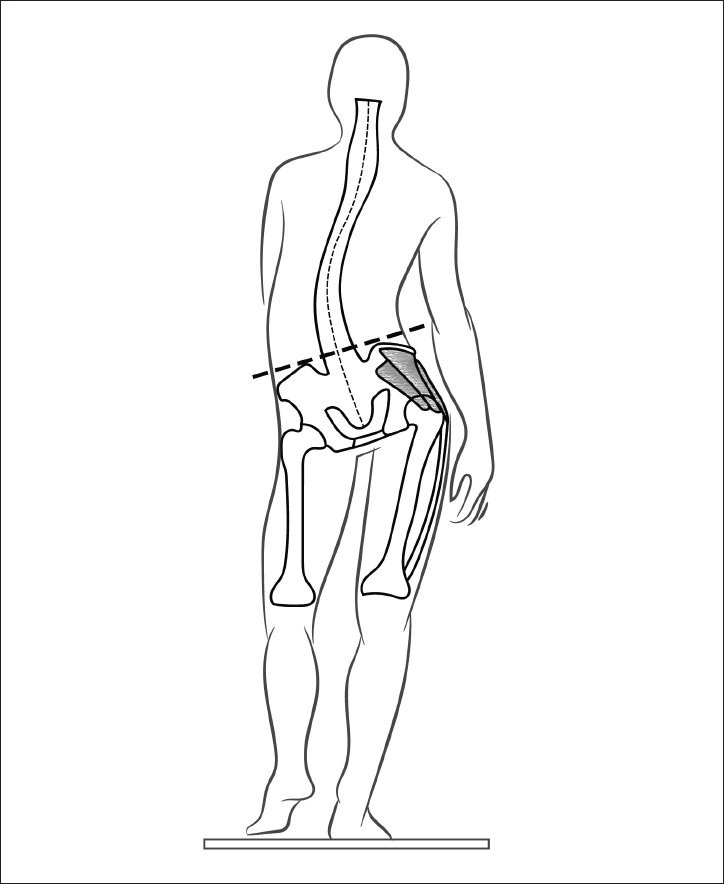

1. Рефлекс переворачивания

Когда ребенок долго лежит на спине, он пытается перевернуться. Его побуждает к этому рефлекс переворачивания (рис. 17).

Он состоит из координации нескольких движений: разворот ног, поворот туловища, разворот плечевого пояса и поворот головы. В дальнейшем эта последовательность движений реализуется при формировании спиралевидной МФЦ. Она начинается от боковых мышц стопы и заканчивается на руке и шее.

Патобиомеханика. Если по какой-либо причине выключаются мышцы, составляющие одну из цепей, возникает деформация статики в виде бокового смещения таза, мышечно-тонического сколиоза, наклона головы в сторону. Поэтому, чтобы убрать одну из найденных деформаций, необходимо восстановить полноценность МФЦ.

Рис. 17. Рефлекс переворачивания.